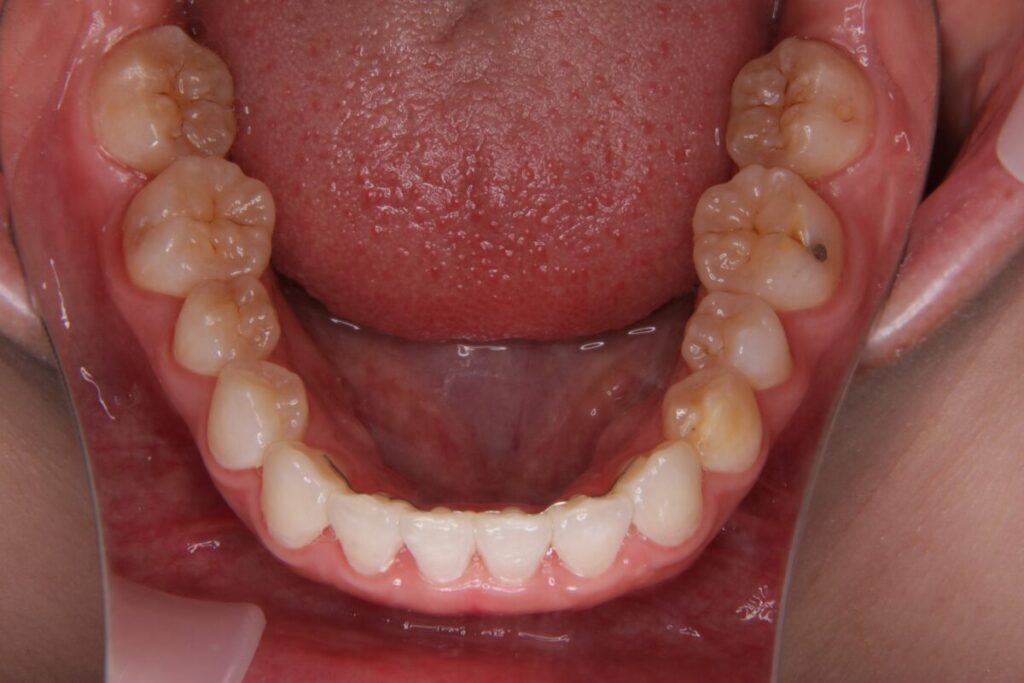

| 患者 | 24歳男性 |

|---|---|

| 主訴 | ガタガタ(叢生) |

| 診断名 | 叢生 |

| 治療内容 | マウスピース型矯正装置(インビザライン) |

| 抜歯の有無 | 非抜歯 |

| 治療期間 | 9か月 |

| 費用(税込) | 836,000円 |

| リスクと副作用 | 痛み等、歯根吸収/歯肉退縮、後戻り、むし歯・歯肉炎の可能性。 |

【医師コメント】

歯並びのガタつき(叢生)を気にされて来院された患者さんです。

骨格的な問題はなく、歯列の幅やスペースの調整によって非抜歯でのマウスピース矯正(インビザライン)が適応と判断しました。アライナーの装着状況も非常に良好で、治療は計画通りスムーズに進行し、約9か月で歯列のアーチを整えることができました。

このような軽度の叢生であれば、正確な診断と日々のセルフケアを両立することで、短期間で無理なく治療を完了できるケースが多く見られます。